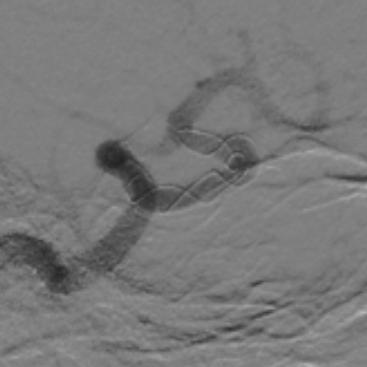

入院后行DSA检查明确右侧颈内动脉眼动脉后下方囊状动脉瘤样影,大小约1.09mm×6.53mm,宽基底,其下方见两个小囊状突起,左侧颈内动脉眼动脉后方及虹吸段均可见小囊状突起。考虑颅内多发动脉瘤。

麻醉成功后,患者仰卧,常规消毒,铺巾, Seldinger法穿刺右侧股动脉,置入5F动脉鞘,置入5F造影管行右侧颈内动脉正侧位及3D造影后,更换6F长动脉鞘,6F中间导管在导丝引导下进入右侧颈动脉分叉端并固定。根据3D造影选择工作体位并放大做路图后,T-track微导管在微导丝引导下进入右侧大脑中动脉,经微导管送入4.0×45mm Tubridge®支架,观察 Marker位置后,于颈动脉分叉附近缓慢释放支架。

Tubridge®释放过程

锚定后,整体回撤至合适位置后,通过张力释放法缓慢释放支架,直至支架完全打开。观察见支架贴壁良好,动脉瘤颈完全覆盖,遂完全释放支架。

全脑DSA正侧位造影示血流通畅。

动脉瘤内造影剂滞留,未填弹簧圈。行Xper CT,观察见支架完全打开,贴壁良好。术程顺利结束。